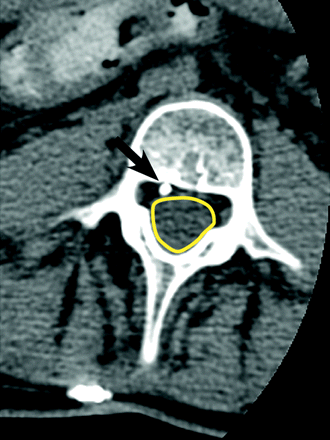

CT

To our knowledge, there is scant literature regarding the use of CT in the evaluation of ITB pump malfunction. Our institutional experience, however, suggests that CT—particularly postcontrast (ie, postinjection of contrast material through the accessory pump port) CT—can be a useful adjunct to fluoroscopy performed during contrast injection for improved identification and characterization of leaks and fluid collections (Figs 8–10).40 Cross-sectional imaging can also aid in visualizing the location of the catheter tip in the spinal canal (ie, within the intrathecal sac) when plain film findings are equivocal (Fig 11).34,41 Two-to-three milliliters of myelographic contrast agent can be injected through the accessory pump port (after successful CSF aspiration) and should be performed while the patient is on the CT table to ensure that the contrast is not overdiluted in the CSF when the images are acquired.34 At our institution, we inject as much as 5–10 mL of thecal sac−compatible contrast material while observing the entire pump-catheter system fluoroscopically and then immediately obtain a CT scan of any areas of concern. Dependent layering of contrast material in the IT space adjacent to the catheter tip suggests a normal study finding. Contrast collection in the subcutaneous, subdural, or epidural spaces suggests leak or tip migration. Limited accumulation of contrast material near the catheter tip with the contrast not appropriately layering in the IT space may suggest focal loculations within the subarachnoid space in the region of the catheter tip.34

An axial noncontrast CT image clearly shows the catheter (black arrow) outside the thecal sac (yellow outline) in the epidural space.